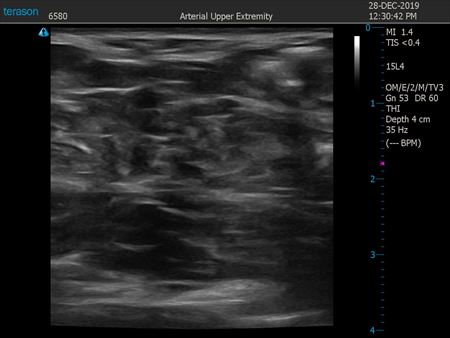

同様に下腹部 ↓ ↓ ↓

↓ ↓ ↓